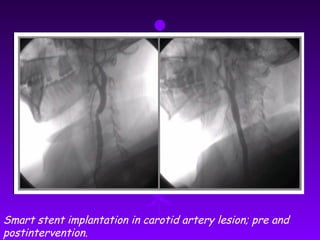

Smart stent implantation in carotid artery lesion; pre and

postintervention.

Smart stent implantationin carotid artery lesion; pre and postintervention.